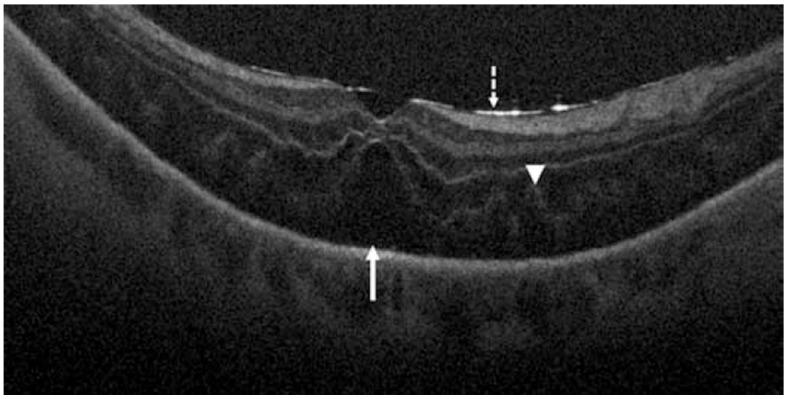

Optical coherence tomography (OCT) imaging has played a pivotal role in the field of retina. This light-based, non-invasive imaging modality provides high-quality, cross-sectional analysis of the retina and has revolutionized the diagnosis and management of retinal and choroidal diseases. Since its introduction in the early 1990s, OCT technology has continued to advance to provide quicker acquisition times and higher resolution. In this manuscript, we discuss some of the most recent advances in OCT technology and techniques for choroidal and retinal diseases. The emerging innovations discussed include wide-field OCT, adaptive optics OCT, polarization sensitive OCT, full-field OCT, hand-held OCT, intraoperative OCT, at-home OCT, and more. The applications of these rising OCT systems and techniques will allow for a closer monitoring of chorioretinal diseases and treatment response, more robust analysis in basic science research, and further insights into surgical management. In addition, these innovations to optimize visualization of the choroid and retina offer a promising future for advancing our understanding of the pathophysiology of chorioretinal diseases.

光学相干断层扫描(OCT)成像在视网膜领域发挥了关键作用。这种基于光的非侵入性成像方式可对视网膜进行高质量的横断面分析,彻底改变了视网膜和脉络膜疾病的诊断与管理。自20世纪90年代初问世以来,OCT技术不断进步,以提供更快的采集时间和更高的分辨率。在本手稿中,我们讨论了OCT技术以及用于脉络膜和视网膜疾病的技术的一些最新进展。所讨论的新兴创新包括广角OCT、自适应光学OCT、偏振敏感OCT、全场OCT、手持式OCT、术中OCT、家用OCT等等。这些新兴的OCT系统和技术的应用将有助于更密切地监测脉络膜视网膜疾病和治疗反应,在基础科学研究中进行更有力的分析,并进一步深入了解手术管理。此外,这些优化脉络膜和视网膜可视化的创新为推进我们对脉络膜视网膜疾病病理生理学的理解提供了一个充满希望的未来。